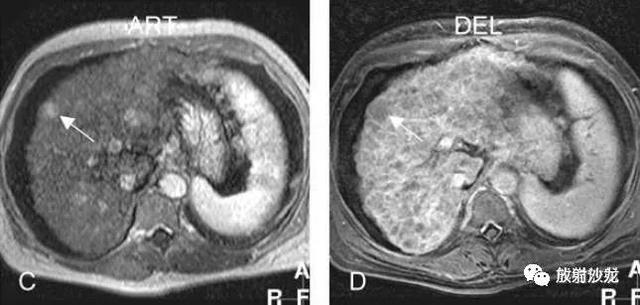

各基本序列信号特征

SSTSE:冠状T2WI,肝硬化,腹水,肝内多发低信号结节;

TSE fatsat:T2WI压脂,所有结节均呈低信号;

ART:动脉期,较大结节强化较明显,其余结节均不同程度有强化;

DEL:延迟期,大结节及其他结节均未见明显肿瘤包膜。

肝硬化,DN,MRI表现:

A~D:影像表现如上所述。

E:反相位,大部分肝结节呈较高信号;

F:同相位,肝内部分结节因铁沉积呈低信号;脾脏亦可见低信号的Gamna-Gandy小体;

G:动脉期,局部放大图像,大结节强化较明显;

H:延迟期,局部放大图像,大结节并未见肿瘤包膜。